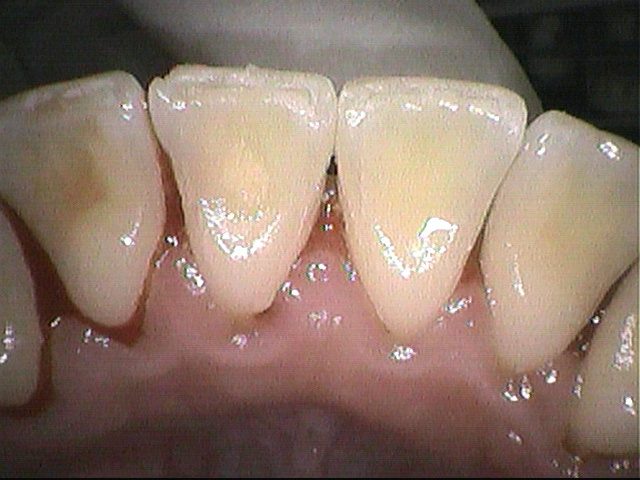

クリーニング後

歯石や磨き残しによって歯ぐきの腫れが強く、出血がありましたが

なるべく痛くないように気を付けながら、できる範囲で除去しました。